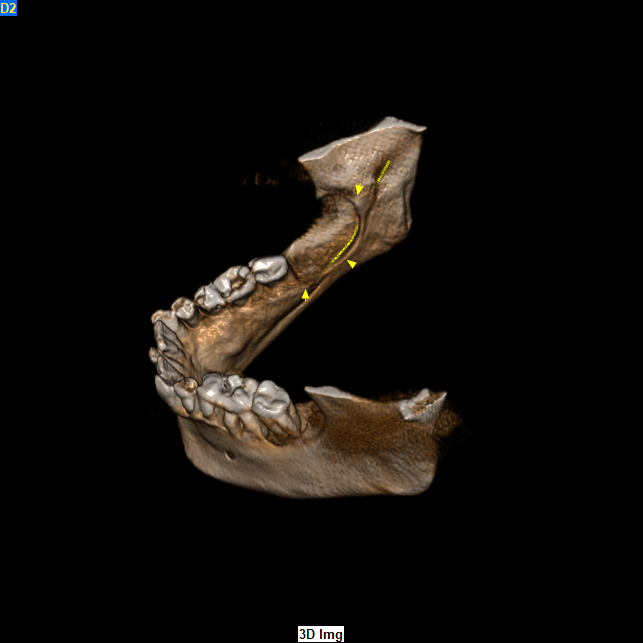

Το CBCT αποκάλυψε την παρουσία εκτεταμένης υπόπυκνης αλλοίωσης στην οπίσθια δεξιά περιοχή της κάτω γνάθου οπισθίως των υπαρχόντων δοντιών η οποία είχε προκαλέσει εκτεταμένη έκπτυξη, λέπτυνση και λύση των συμπαγών πετάλων, ενώ είχε απωθήσει και τον πόρο του κάτω φατνιακού νεύρου προς τα κάτω.

CBCT 12/2020